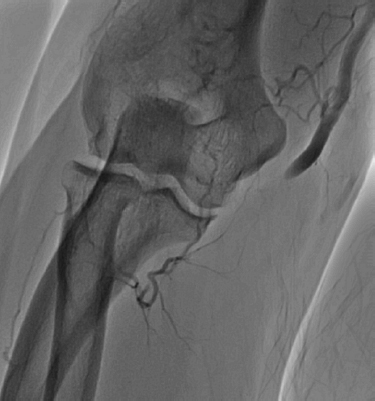

His presentation was consistent with acute limb ischemia, and emergent angiography revealed an occluded right brachial artery at the antecubital segment (Figure 1). Aspiration thrombectomy and mechanical rheolytic thrombectomy were attempted multiple times with slight improvement in blood flow. There was persistent large thrombus burden, and subsequent placement of fountain catheter and catheter directed thrombolysis were performed. Repeat angiography 12 hours after lytic infusion showed return of flow within the brachial artery but persistent occlusion in the ulnar artery (Figure 2). Multiple attempts of angioplasty were performed at the level of the bifurcation of the ulnar and radial arteries; the ulnar artery occlusion persisted. Angiography did show appropriate flow in the radial artery, an intact palmar arch, and retrograde filling of the ulnar artery (Figure 3). At this time the procedure was terminated, and the patient was sent to the CICU for observation.

Figure 1

Figure 1. Occluded brachial artery at initial angiography.